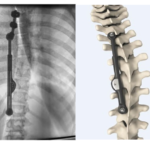

Evolution of Instrumentation in Scoliosis

Courtesy: Dr Muralidharan Venkatesan, Apollo Hospitals Consultant Spine Surgeon